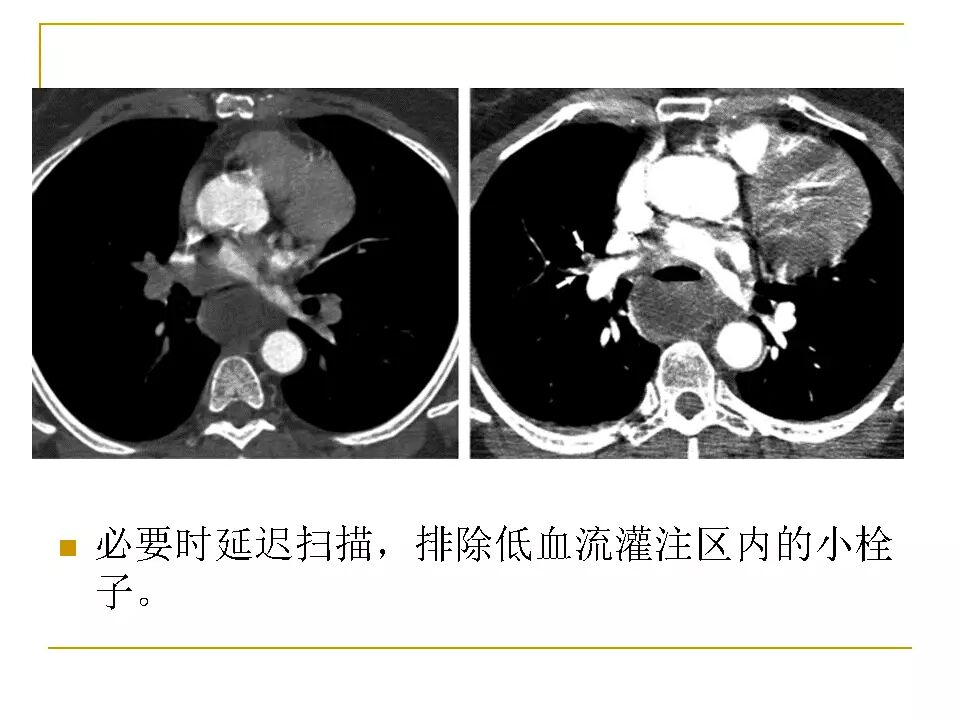

【RadioGraphics】肺动脉栓塞CTA